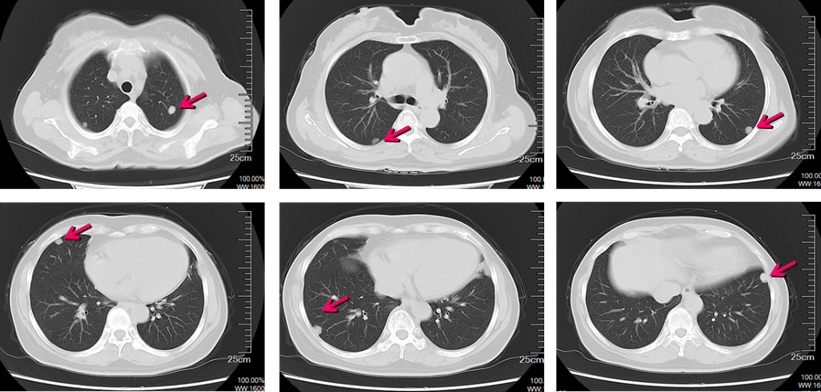

2017-12肺部平扫CT+尿路成像(CTU)示(图1-图3):双肺多发转移瘤,共10余个,最大径约为1.7 cm。左肾见混杂密度肿块,范围约6.5*6 cm,左肾癌可能大,累及左肾盂、下组肾盏结构、左肾静脉。膀胱镜示:左侧输尿管口可见喷血。

图1. 胸部CT影像提示双肺多发转移

术后靶向治疗:患者在行根治性手术治疗后,继续使用培唑帕尼(800 mg/PO/QD)2个月后于(2018-6)复查,胸部及肾脏CT平扫示:与旧片(2018-3)对比,双肺结节无明显改变,左肾术后。之后患者按照每间隔3个月复查一次,至2019年3月,该过程中患者病情平稳,转移灶控制良好,使用培唑帕尼时无明显不良反应。肿瘤PR进一步缩小,接近CR。影像学改变如下图(图4-5)。

图4. 培唑帕尼治疗前后肺CT变化